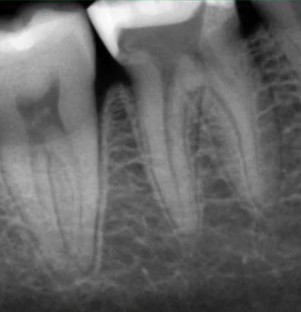

Кхалил Абаноуб Адли Абдуллах: портфолио (4)